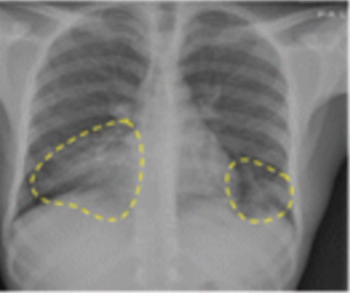

A multi-year agreement with a large Chile-based supplier of raw iodine is part of GE Healthcare’s commitment to increase the production of iodinated contrast media, commonly used in computed tomography imaging, by 30 million annually in 2025.